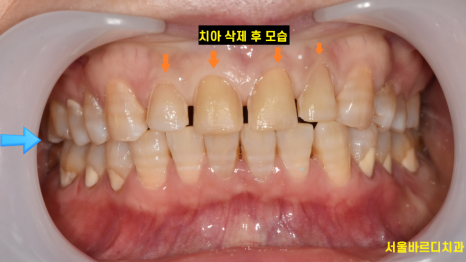

라미네이트가 부착이 유지될 수 있게

최소한으로만 삭제한 모습입니다.

처음 상태와 비교해보면

삭제를 거의 진행하지 않았어요!!!

250220

살짝 다듬은 정도죠~~

화살표를 보시면

크게 달라진게 없답니다.